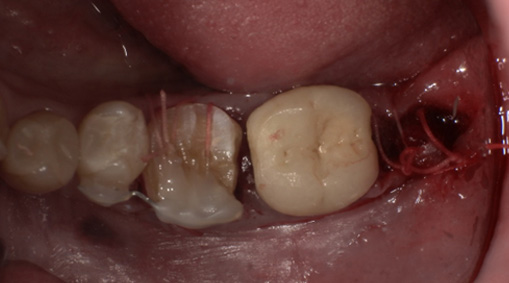

術前・術後の比較

| 術前 | 術後 |

|---|---|

![]() |